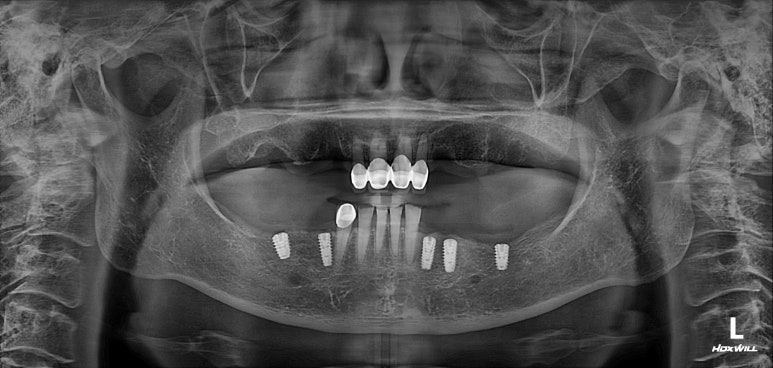

위턱에 뼈이식을 하면서 임플란트 1차 수술을 먼저 시행했습니다.

아래는 이제 어느 정도 모양을 잡아드린 상태이고, 이제 어느 정도 아물었을 위턱 부위에 임플란트 수술을 시행했습니다.

왼쪽 3개 오른쪽 3개 총 6개의 임플란트를 뼈이식과 함께 수술해드렸어요.

위턱 임플란트 수술 후 3개월의 치유기간을 거친 후 임플란트 2차 수술을 했습니다.

위 임플란트들도 뚜껑이 생긴 것을 보실 수 있으실거에요.

치유지대주를 연결해 주었습니다.